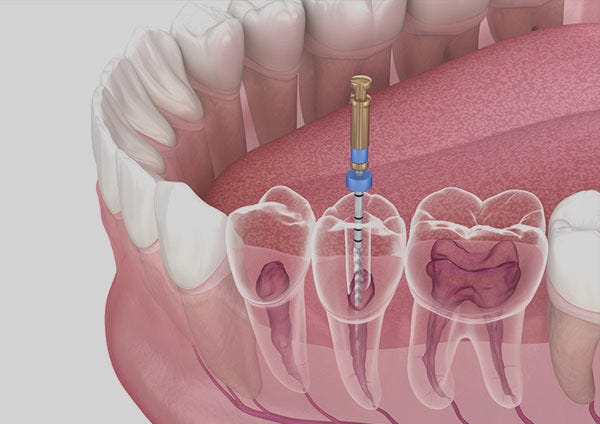

If you’re experiencing severe tooth pain or sensitivity, you may need a Root Canal Treatment in RR Nagar At Symphony Smiles Dental, the expert endodontists use state-of-the-art technology to perform this procedure with precision and minimal discomfort. Gone are the days when root canals were dreaded — here, they are virtually painless and highly successful.for more details visit here:https://medium.com/@symphonysm....iles51/root-canal-tr